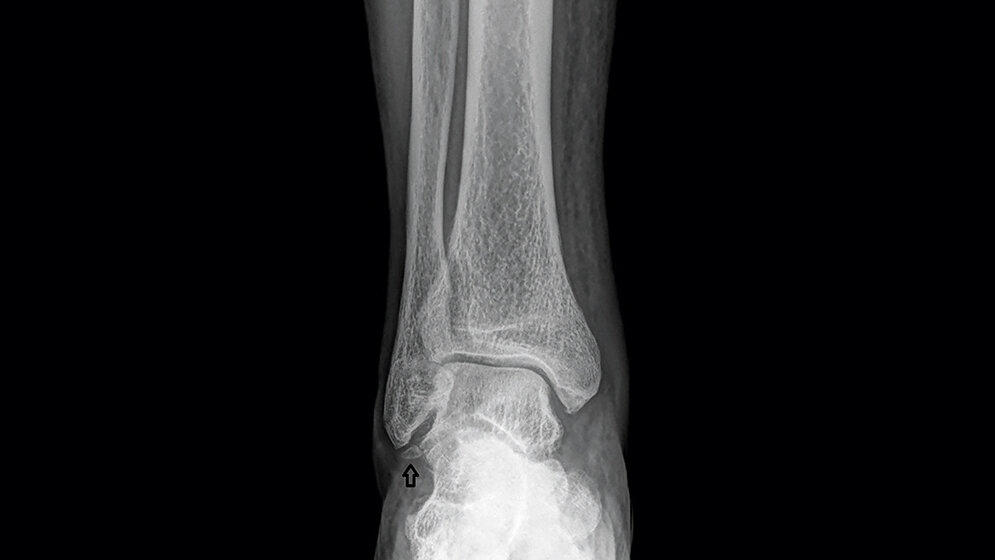

Os subfibulare und subtibiale sind gelegentlich vorkommende akzessorische Knochen des Sprunggelenks. In den meisten Fällen sind sie asymptomatisch. Sie können malleoläre Frakturen vortäuschen. In Fällen von chronischen Schmerzen und Instabilität bei vorliegenden lokalen Akzessoria ist die operative Entfernung die beste Therapie.

Os subfibulare and subtibiale are low prevalence accessory bones of the ankle. In most cases they are not associated with symptoms. They can mimicking malleolar fractures. In cases of chronic pain and instability associated with this accessory bones, surgical ex‧cision is the best therapy.